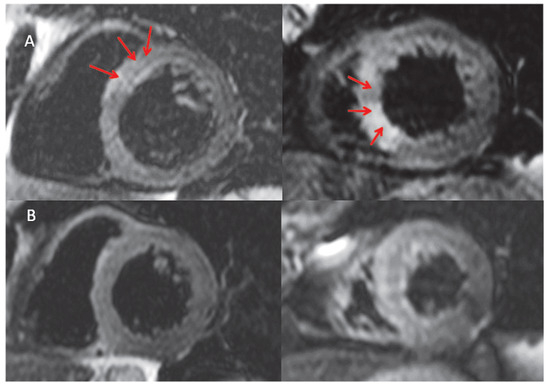

Case Report

Figure 3. A. Cardiac Magnetic Resonance (CMR) scan (Siemens 1.5T, Erlangen, Germany) 5 days after admission. On the STIR images (T2 weighted sequences, short tau inversion recovery) myocardial oedema was seen in the antero-septal and inferior-septal wall at the mid ventricular level (arrows). B. Follow up CMR scan performed at 3 months showing complete resolution of the septal oedema.